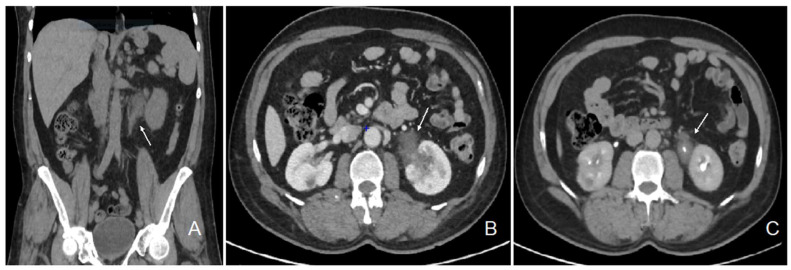

The patient initially consulted our emergency service for recurrent left para-lumbar region pain. Abdominal computed tomography (CT) scan and renal sonography highlighted the presence of a polypoid tumor of the left ureter and renal pelvis causing moderate left uretero-hydronephrosis with moderate kidney failure (Figure 1) and locoregional enlarged lymph nodes. At the time, the right urinary tract was intact, and his biology showed a plasma creatinine of 1.35 mg/dL with an estimated glomerular filtration rate (eGFR) of 53 mL/min/1.73 m2 according to the CKD-EPI formula. Usual biological tests showed a normal calcium level and a mild 25 (OH) vitamin D deficiency with mild secondary hyperparathyroidism, and slight lymphopenia (Table 1). Urine cytology showed discrete to moderate nucleus abnormalities compatible with a low-grade papillary kidney carcinoma. Subsequently, the patient underwent a left nephroureterectomy.

A macroscopic pathological examination revealed a granulomatous aspect of the distal margin of the left ureter progressing towards the renal pelvis, holding a papillary lesion measuring 5.5 × 4.5 × 4 cm. Microscopic analysis revealed an intense inflammatory reaction of the proximal ureter and pelvic cavities. The inflammatory reaction coalesced into epithelioid granulomas with multinucleated giant cells. The epithelial lining showed a reactive aspect, with the formation of intraluminal pseudopolypoid formations without evidence of neoplastic tissue (Figure 2).